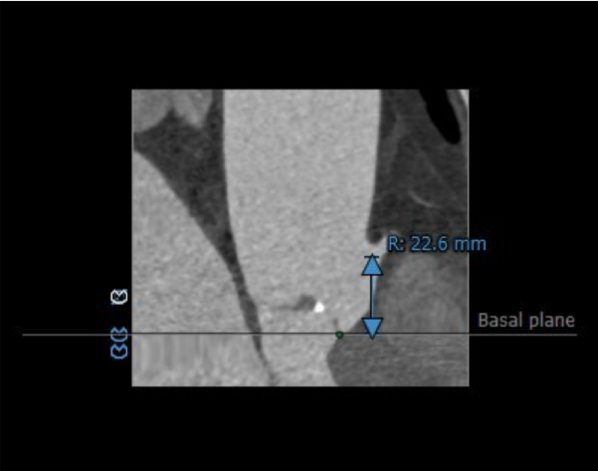

主动脉瓣瓣环周长77.4mm,平均周长径24.6mm。CT数据显示该患者为Type1型二叶式主动脉瓣,瓣叶轻度增厚,中度钙化,钙化分布散在分布于瓣叶边缘,左右瓣叶交界区钙化分布较重,左右瓣叶融合并形成坚强钙化嵴,左右冠开口高度可,未见冗长瓣叶,冠状动脉散在钙化。

瓦氏窦内径较大,窦管交界内径可,升主动脉扩张

主动脉根部评估